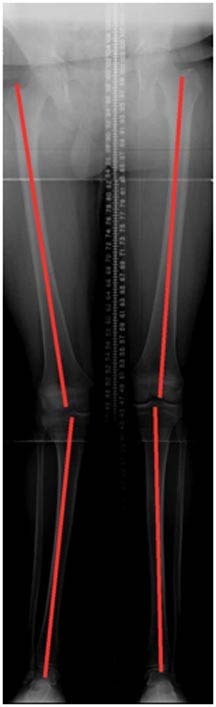

The patient is a 17 year old male who had a motorbike accident with an upper tibial fracture just below the growth plate. He developed a knock kneed (valgus) deformity which caused him substantial knee pain.

2.Standing alignment radiographs show that he has developed a knock-kneed (valgus) deformity on the right side.